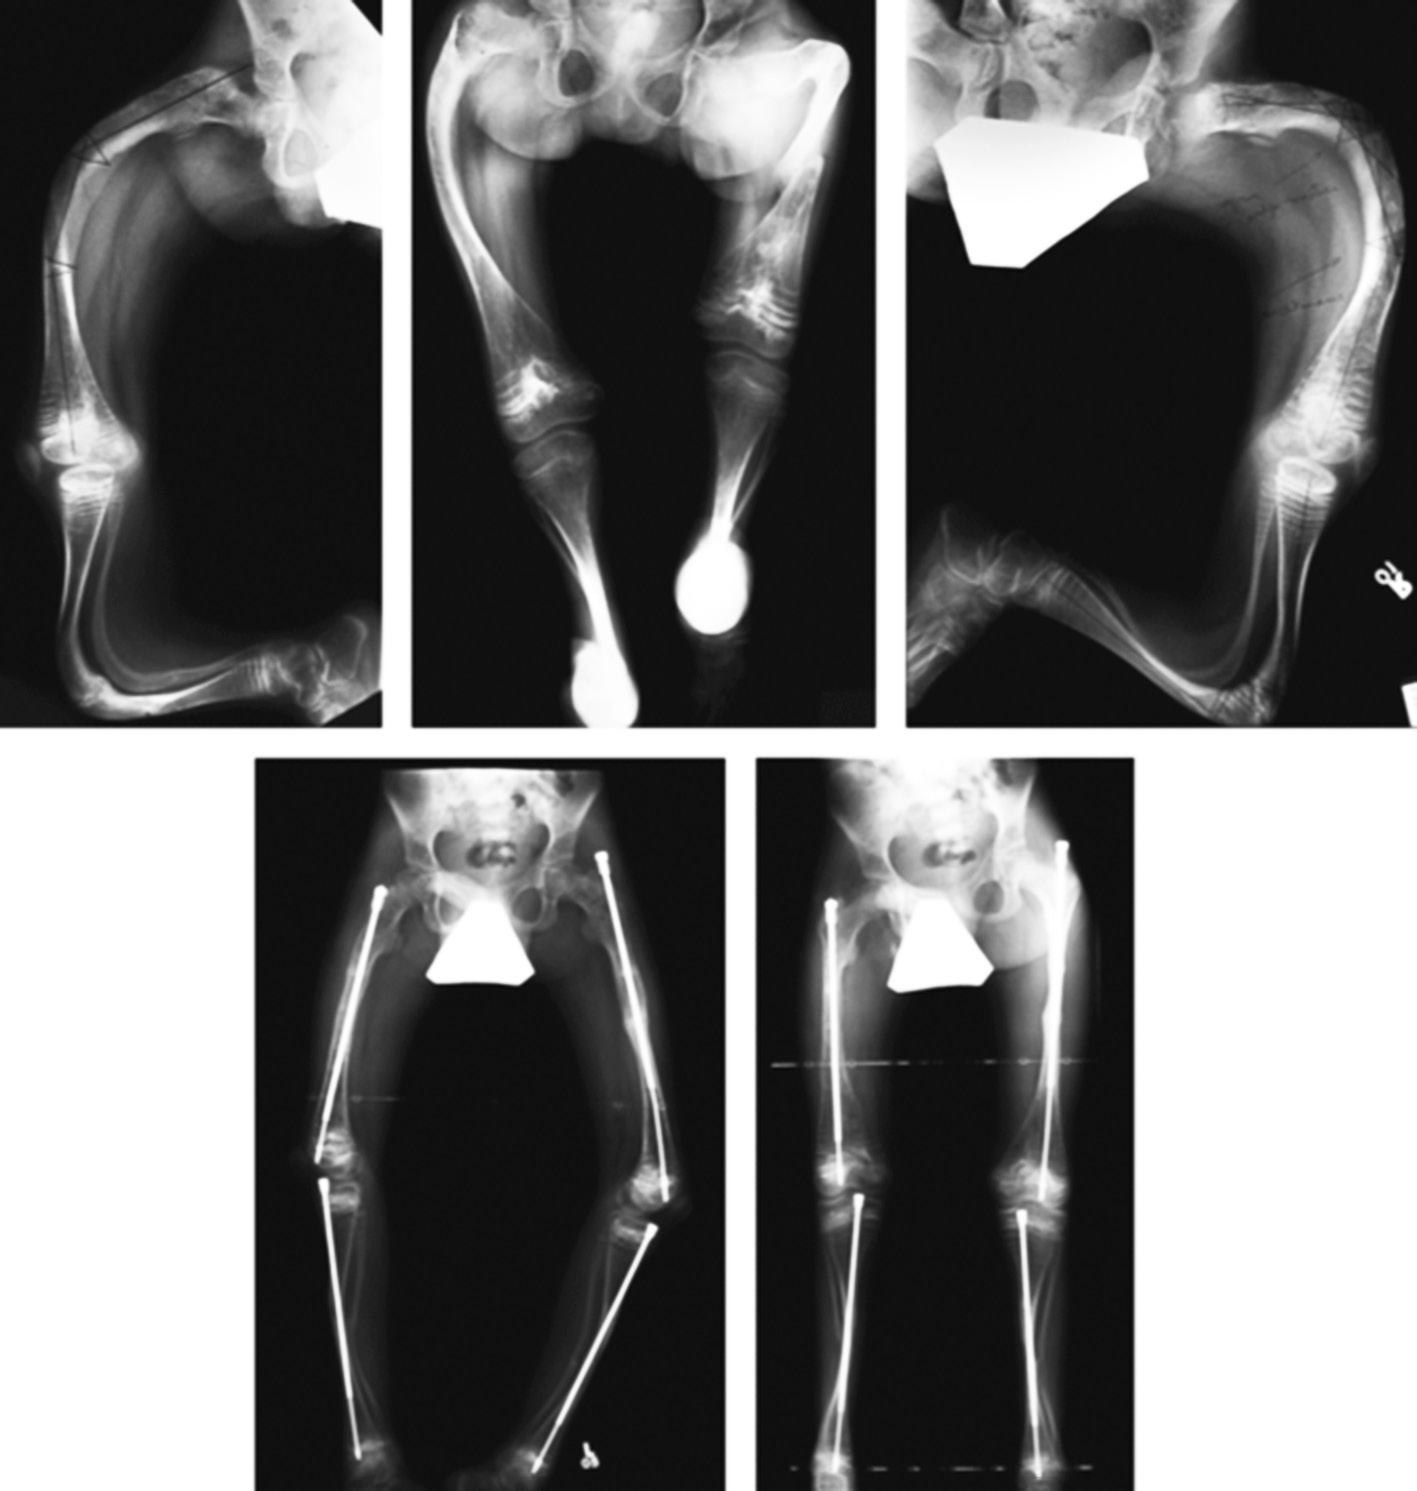

Diagnosis

OI diagnosis is based on clinical signs and anamnestic data–fractures in the perinatal age or high incidence of fractures among relatives. Genetic testing is used to diagnose milder forms of OI, when patients do not have characteristic phenotypic signs but are susceptible to fractures [17]. In some countries, genetic research is used to eliminate child violence in the family as a possible cause of frequent fractures. Thus, according to a study, 11 of 262 fractures in children were presumed to be caused by child abuse in the USA. Based on the results of a genetic study, OI was detected in six of them [18]. OI type is determined by a combination of these data in accordance with the classification given in the article Nosology and Classification of Genetic Skeletal Disorders and according to genetic analysis data. Determining the OI type is important to assess disease severity, predict the possible complications of surgical treatment, and choose the most effective drug treatment. Thus, in patients with OI type V, the probability of hypertrophied callus formation after surgical treatment is high (Fig. 1) [10, 11]. Understanding the genetic mechanisms of OI development opens up prospects for targeted treatment. For example, intravenous administration of bisphosphonates in patients with OI of type VI is less effective than the use of denosumab [19].

Fig. 1. Hypertrophic callus after surgical treatment of a patient with type V osteogenesis imperfecta

The analysis of the genome of OI patients or their relatives allows determining the possibility of OA for their child. With the help of next-generation sequencing technology, it is possible to analyze a whole exome by using panels with all known genes responsible for OI [20]. To date, molecular diagnostics are 97% accurate [21]. Routine OI screening is limited to ultrasound scanning. Fractures can be detected in the 20th week of pregnancy, and assessment of OI severity is possible [5].